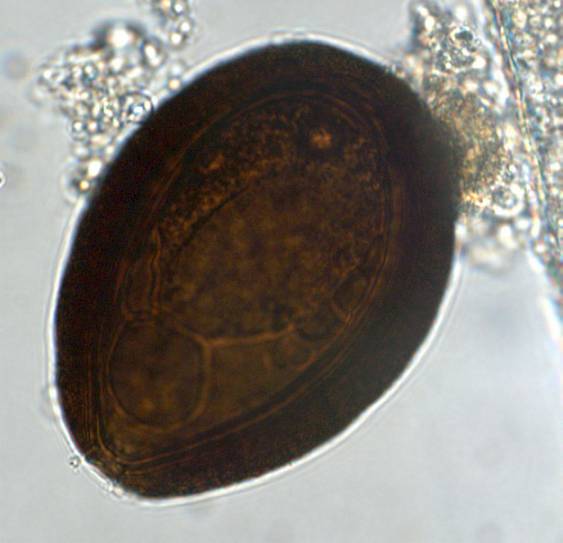

Coproscopy

Trematodes